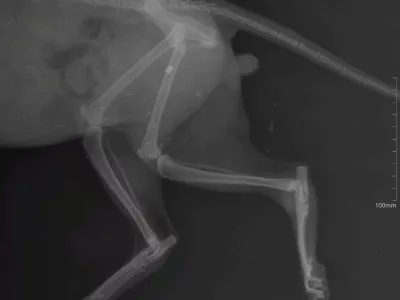

Za nas prazniki, za živali nočna mora Praznično pokanje in tihe žrtve: kako pirotehnika prizadene živali